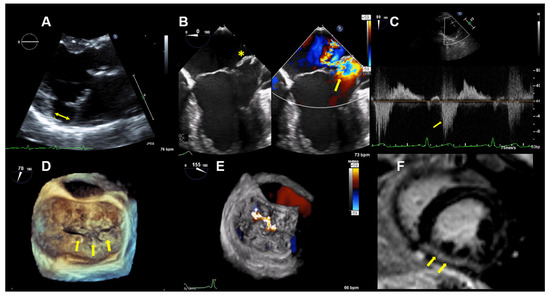

Figure 3.

Case 2: Summary of the key findings from multimodality imaging. (A) The mitral annular disjunction (yellow double arrow) is visualized in a 3D transthoracic echocardiography view. (B) A 4-chamber transesophageal echocardiographic (TEE) view shows the bi-leaflet prolapse, which is more pronounced in the posterior leaflet (yellow asterisk), thus resulting in an eccentric mitral regurgitation (MR) jet, as seen in color Doppler (right; yellow arrow). (C) The pulsed-wave Doppler profile derived in the left superior pulmonary vein shows a reverse systolic flow (yellow arrow) as a sign of severe MR. (D) Larger prolapse segments are marked with a yellow arrow in a 3D TEE view. (E) The MR is seen in a 3D TEE enface view with color Doppler. (F) Cardiac magnetic resonance imaging reveals focal mid-wall and subendocardial fibrosis in the mid-inferior wall (yellow arrows).

TTE and TEE imaging confirmed the diagnosis of a bi-leaflet prolapse with myxomatous changes of both mitral leaflets (Barlow’s disease) and significant MR (Figure 3). A Zio XT patch monitor (iRhythm Technologies, San Francisco, CA, USA) showed frequent PVCs, nonsustained ventricular tachycardia (nsVT), and supraventricular tachycardia (SVT). Betablocker therapy was initiated.

CMR imaging confirmed a mildly impaired LV function (LVEF 53%) and a regurgitant fraction of 45% consistent with moderate-severe MR. The extracellular volume fraction was 34% (normal limit <30%), consistent with diffuse myocardial fibrosis. Focal mid-wall and subendocardial fibrosis was observed in the mid-inferior wall (Figure 3F).

Thus, based on all of the findings, an increased perioperative morbidity in this MR patient was hypothesized and, also, to comply with the patient not wanting surgery, the decision was made to proceed with a percutaneous MV repair strategy. Subsequently, two MitraClips (XTR) (Abbott Vascular, North Chicago, Illinois, USA) were implanted with an excellent result, with minimal residual MR (Figure 4). One year after MitraClip implantation, the patient reported significantly fewer palpitations, and her exercise tolerance was normal. TTE imaging documented normal LV function with a LVEF of 60%, normal pulmonary artery systolic pressure and mild, late-systolic MR. Using Zio XT patch monitoring, a marked reduction in PVCs from 18.7% to 1.2% and rare SVT were seen, and no nsVT occurred (data are in Figure 5).